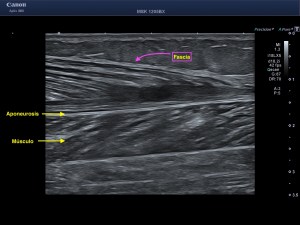

La radiografía revela aumento de las partes y se refrenda en la ecografía como puedes ver en la imagen aunque aún no hay afectación en el hueso en el caso que te presento hoy.

Ecografícamente y debido a su levedad, en el caso de hoy solo observamos cambios en las partes blandas de la cara lateral de la cabeza del quinto metatarsiano, este tejido se muestra heterogéneo, la cortical del hueso ligeramente prominente sin afectación de la misma.